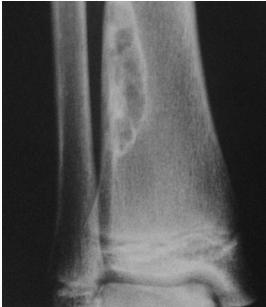

Giant-Cell Tumor

- Unknown origin:

- Giant cells abundant

- Behavior:

- One third benign

- One third locally aggressive

- One third (less) with distant metastasis

- Young adults

- Common sites:

- Around knee

- Proximal humerus

- Distal radius

Radiological Features

- Eccentric lesion:

- Radiolucent

- Soap bubble

- Abuts (adjacent) against the joint

- Thin cortex

- Margins may be clear / unclear:

- Depends on aggressiveness

- Treatment:

- Curettage & bone grafting

- More wide excision in recurrent and aggressive lesions

Source: Bone Tumors A Practical Guide to Imaging